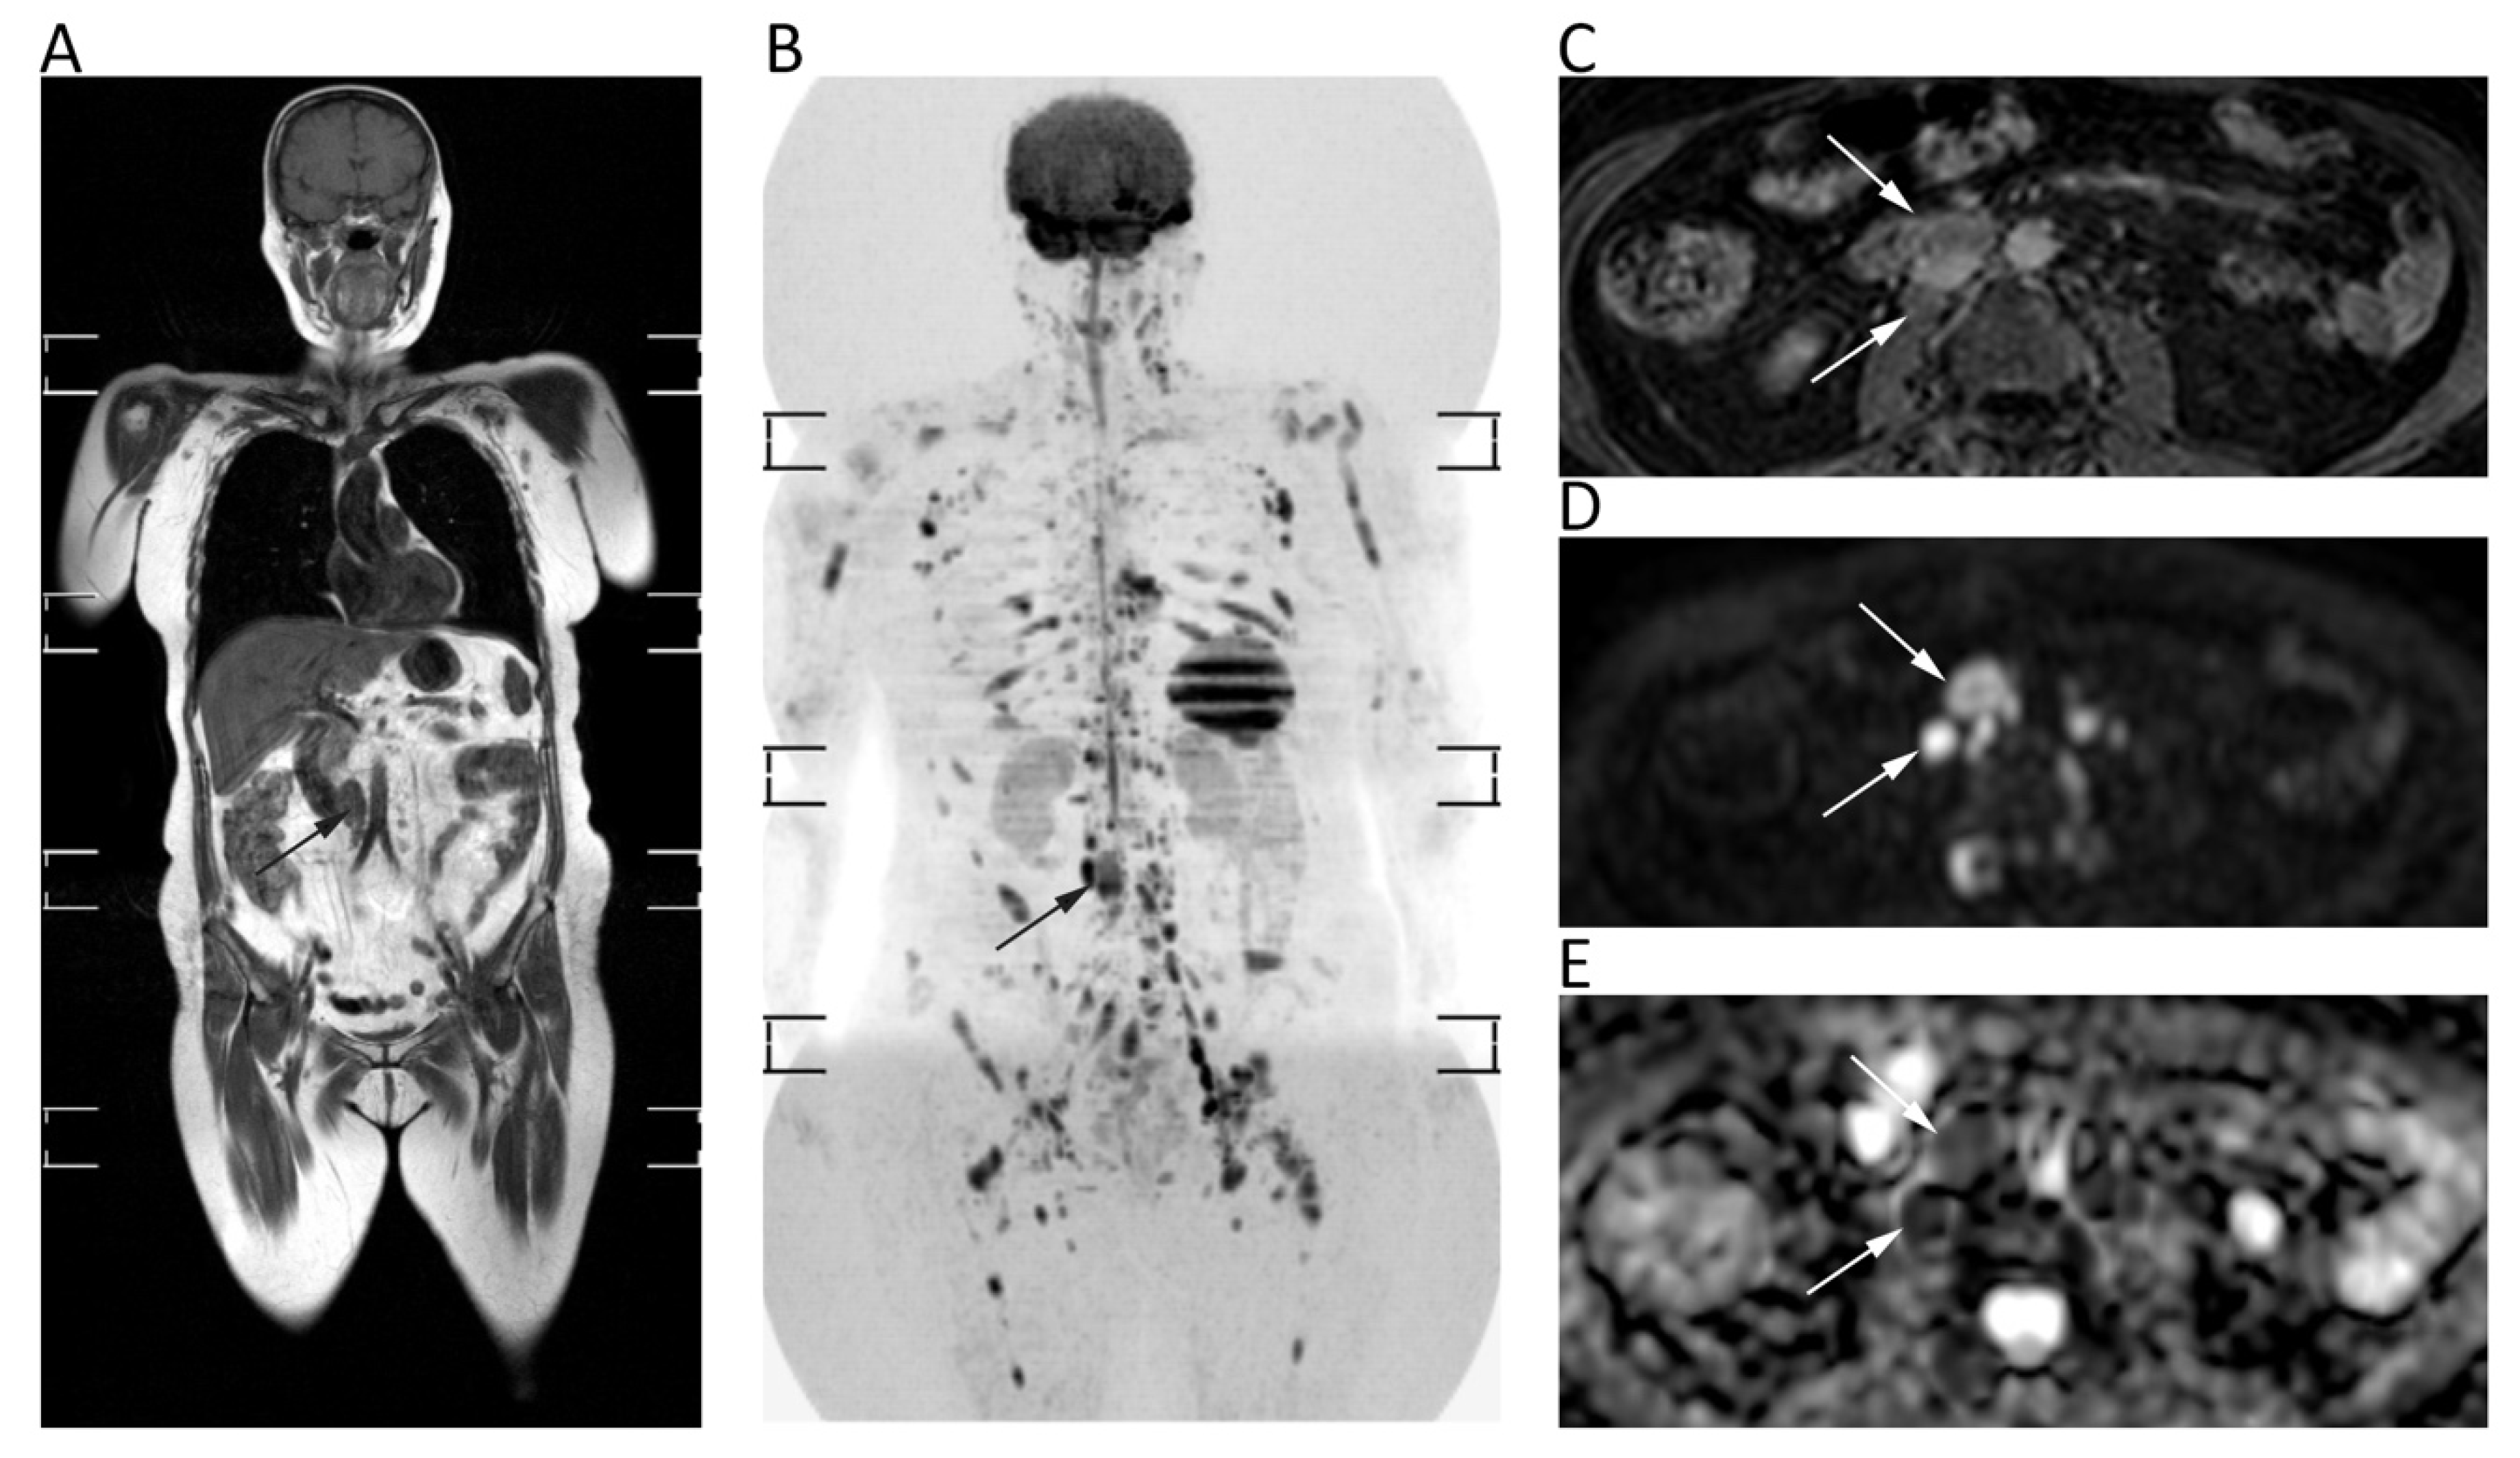

12. Lymph Nodes and Spleen

| Lymph Nodes and Spleen | Albano, D.; et al., Eur. J. Radiol. 2016 [87] | Prospective; 68 patients with FDG-avid lymphoma. Comparison between WB-MRI with DWI and FDG-PET/CT. 1.5T MRI. | Excellent agreement between WB-MRI and FDG-PET/CT stage (k = 0.88; p < 0.05); WB-MRI stage was equal to FDG-PET/CT stage in 91.2% (62/68; in particular, 35/37 Hodgkin lymphoma, 27/31 Non Hodgkin lymphoma). Sensitivity of WB-MRI for splenic involvement was 100%. |